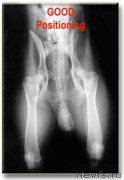

n'yuf-ne-chaynica (ньюф-не-чайница) Здесь явный подвывих сустава. Вероятнее всего С или D

На обеих(обоих?) лапах.Скорее всего ближе к Д.

Собака положенна практически правильно.

Собака уложена правильно. Немного перекошены тазовые кости, но это не принципиально. Нет смысла делать снимки лягушкой. Сложно зафиксировать правильно собаку

А мне кажется подвывих на правой лапе, где R стоит, и не сильный.

Вертлюжные впадины не разбиты и ярко выражены, но не закрыты, головка бедренной кости не деформирована, но не прижата плотно, чуть наклонено правое крыло таза, но не сильно.

Двигаться должна нормально, если и беречь, то правую лапку, это видно хорошо по походке.

Нужно чтобы врач описал..., а то сколько людей столько и мнений. Я вижу, что вертлужная впадина достаточно сильно уплощена и головка бедра тоже изменена, вероятно - D.

По ТЗБ, да правый плохой совсем, да и левый не очень, но больше смутили коленные суставы, сильный выверт бедренной кости относительно большеберцовой, может разрыв или растежение крестовидной связки, не так выглядит коленный сустав, другой разворот.

Смимок однозначно некорректный, нужно переделать и врач готов дать консультацию по телефону, но по новому снимку, и снимку коленного сустава в другой проекции.